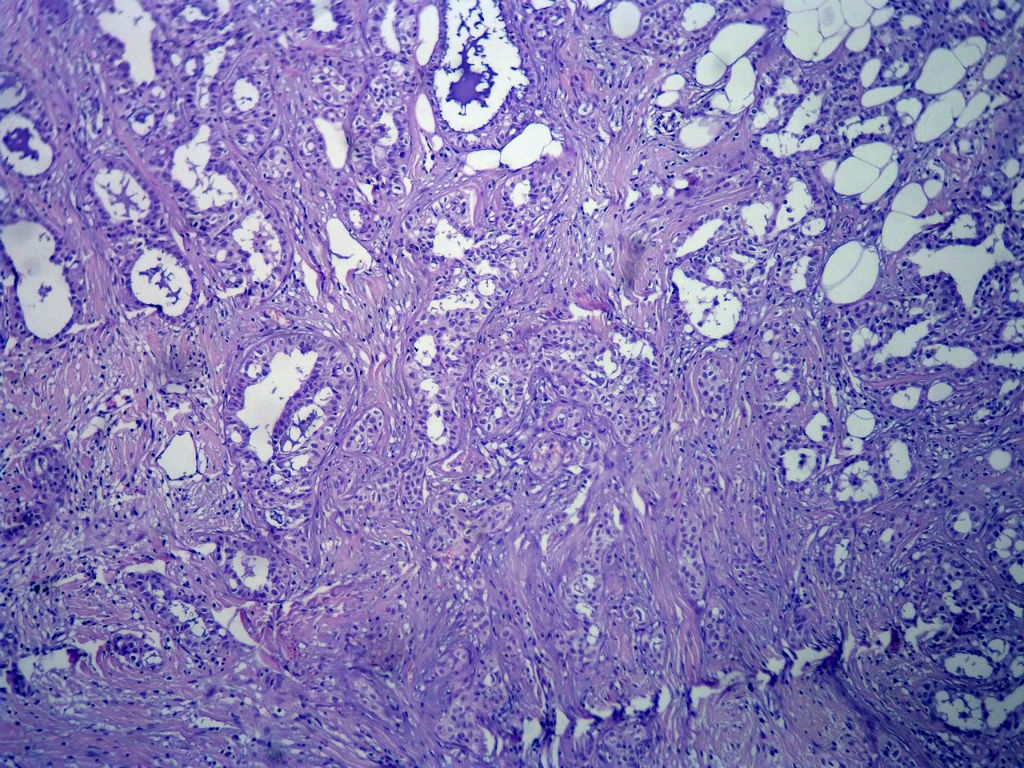

今天的一例术中冰冻。女,49岁,乳腺肿块。人气不旺,换个标题

腺病?癌?其他?(12楼常规,24楼免疫组化及会诊结果)图1

标签:浸润性导管癌 分泌癌 硬化性腺病

乳腺分泌型癌

1. Most likely no invasive cancer

2 Sclerosing adenosis

3 Ductal epithelial hyperplasia

4. Bundles d Smooth muscle?

导管是乎可见双层上皮,部分上皮增生并有一定异型,考虑硬化性腺病,待石蜡。

导管可见双层上皮,部分上皮增生并有一定异型,考虑硬化性腺病

腺体与腺体之间的对比差异太大,不放心,不除外是癌,如果是我的病例,再次取材冰冻

占楼传常规1-11为冰对。